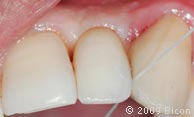

66. Вид интегрированной коронки (IAC).

67. Вид интегрированной коронки (IAC).

68. Вид спереди.